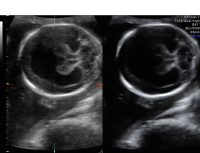

Holoprosencephaly is a severe abnormality in the development of the brain. In normal development, two sides of the brain develop. Holoprosencephaly is a condition in which the two sides of the brain do not separate normally. This condition occurs in approximately one in 8,000 second-trimester pregnancies.

If suspected, a detailed ultrasound will be performed to look for other abnormalities. A fetal MRI may be recommended to provide a more detailed view of the brain. As other anomalies and genetic abnormalities may be associated with this finding, genetic counseling and testing are recommended. Prenatal consultations with pediatric neurology specialists may be recommended to discuss the condition and its prognosis. Prenatal care will be managed by a maternal-fetal medicine specialist, an obstetrician with special training and expertise in high-risk pregnancies.

Unfortunately, the prognosis for holoprosencephaly is poor. Survival is possible in less severe cases, however with severe disability. There is no treatment for holoprosencephaly.